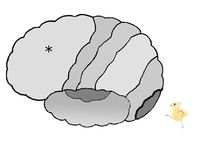

図は、左の大脳皮質を左から見た図です。

網膜からの視覚性情報は、後頭葉の視覚野へ届くことで「見えた!」と感じるのです。

大脳皮質の図において、*印は 前頭葉 頭頂葉 後頭葉 側頭葉 である。